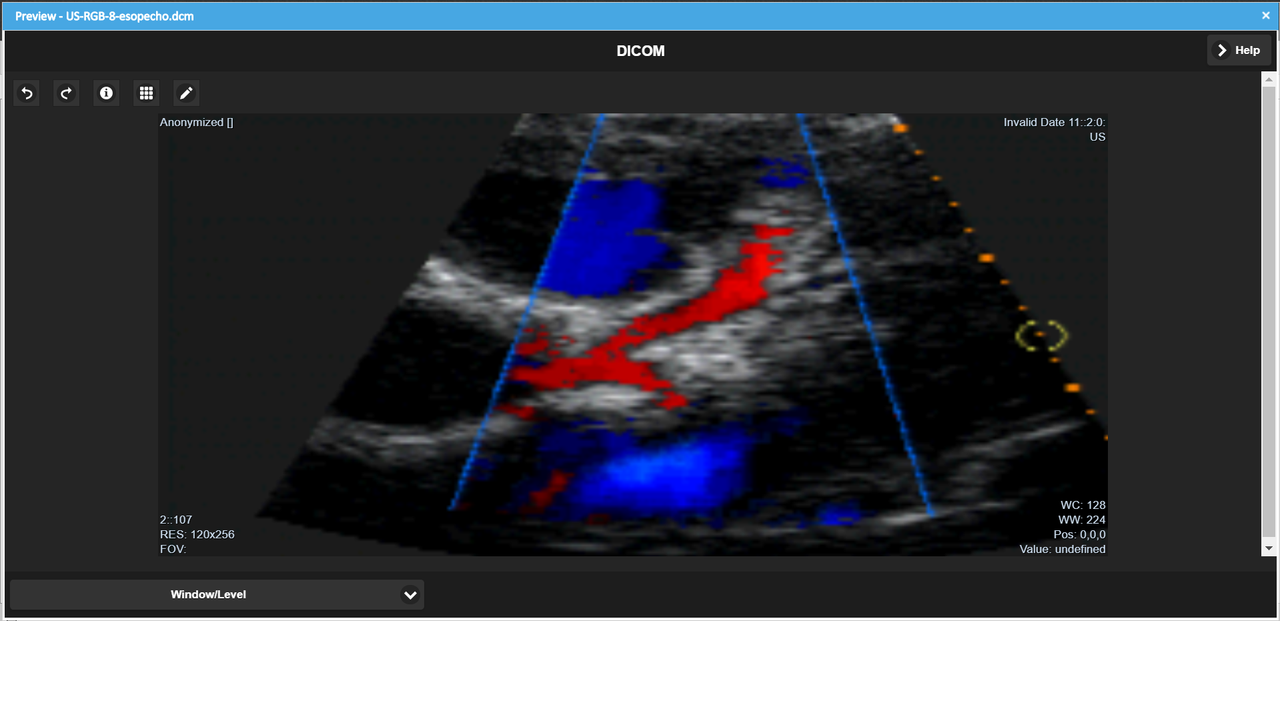

Ab LogicalDOC 8.3 ist die Vorschau von medizinischen Dokumenten im DICOM-Format verfügbar.

Einzelheiten der Funktion

- Anwendbare Farbfilter

- Animation von Bildsequenzen

Screenshots